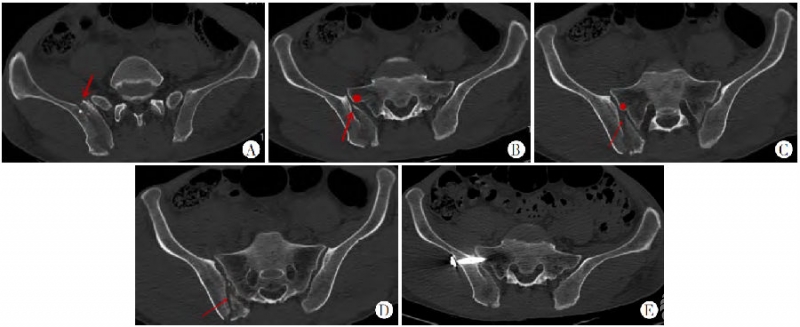

新月形骨折病例解剖学分型II型(骨折线为斜形,27例):

同一患者的CT横断面不同层面。

图6 A层面看,无法有效分入Day分型;B骶髂关节波及小于三分之一,此层面按照Day分型可分入Day I型;C骶髂关节波及一半左右,按照Day分型可分入Day II型;D骶髂关节波及大于三分之二,按照Day分型可分入Day III型。A~D.横断面特点:新月形骨折内板骨折线(红箭头所指)与骶骨侧嵴密切(红色圆点所指)相关。骶骨侧嵴出现前骨折线的位置比较随机(A),骶骨侧嵴(红色圆点)出现后,髂骨内板骨折线起点(红色箭头所指)与骶骨侧嵴紧密相关(B、C);骶髂关节被累及的范围由前1/3(B)、1/2(C)到后1/3,(D)往下的层面骶骨侧嵴突出不明显;在新月形骨折线为斜形时均存在这种现象;由此可见,同一患者在不同层面根据Day分型,就可分别分入Day I、II、III型了,这种缺陷显然削弱了Day分型的效率。E.由于髂骨外板相对完整,宜打入骶髂螺钉固定。

图7 Calafi等[4]提出的不能分入Day分型的情况,与本图A类似,只是CT横断面的某个层面

新月形骨折病例解剖学分型II型(骨折线为横行,3例):

当新月形骨折线为横行时,这种按照Day分型的变异就变得相对轻微。

图8 A~C.横断面特点:横断面由近及远各层面显示新月形骨折内板骨折线(红色箭头所指)起自骶骨侧嵴(红色圆点),基本垂直骶髂关节面走行,也随层面不断变化,骨折线起点在各层面均与骶骨侧嵴紧密相关,骶髂关节被累及范围变异较斜形骨折线小

图9 A~C.冠状位表现:新月形骨折内板骨折线(红箭头所指)与骶骨侧嵴(红色圆点所指)密切相关,冠状位骶髂关节累及范围随层面变异程度较横断面轻

冠状位表现可以作为新月形骨折病理解剖学分型的一个重要参考。